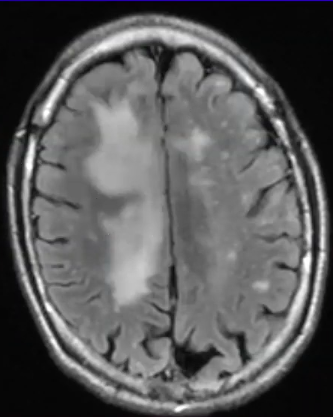

What is the diagnosis and why?

JC virus causing progressive multifocal leukoencephalopathy

• diffuse white matter lesions, no mass effect, do not enhance with contrast